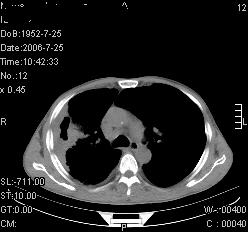

患者,男,54岁,咳嗦,咳痰20天。抗炎治疗2周。现esr76mm/h,目前患者症状明显好转,但发现两次ct片未见明显变化。两次分别做与7.25、7.31。第一次诊断右肺上叶炎症累计胸膜。大家看,从影像上内排除结核吗?

结核的可能性非常大,右上肺病变应该考虑干酪性肺炎。理由:

1.纵隔内多发淋巴结肿大。

2.esr76mm/h。

3.虽经抗炎治疗肺窗病灶有所吸收、减小,但纵隔窗病灶形态、密度、范围无明显变化。如果是单纯的大叶性肺炎,“抗炎治疗2周,目前患者症状明显好转”病灶应该基本消散了,至少也处于吸收消散期,密度变淡、范围变小。同时本病例所示其内的密度不均匀,见多发大小不一空洞样影也不符合大叶性肺炎吸收消散期表现。

病灶特点:片状 索条 结节混杂影,部分融合,密度不均,广泛累及相应胸膜.

临床治疗;二周未吸收.但症状好转.

多考虑:肺结核.